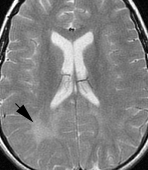

麻疹包涵体脑炎 (MIBE) 是免疫功能低下个体麻疹感染的一种罕见表现,通常在麻疹感染后 1 年内出现。疾病起病为亚急性,进行性神经功能障碍在数周至数月内发生。亚急性硬化性全脑炎 (SSPE) 是一种罕见的退行性中枢神经系统疾病,其特征是行为和智力恶化以及癫痫发作,通常发生在野生型麻疹病毒感染后 7 至 11 年。2 岁之前感染的儿童感染率最高。